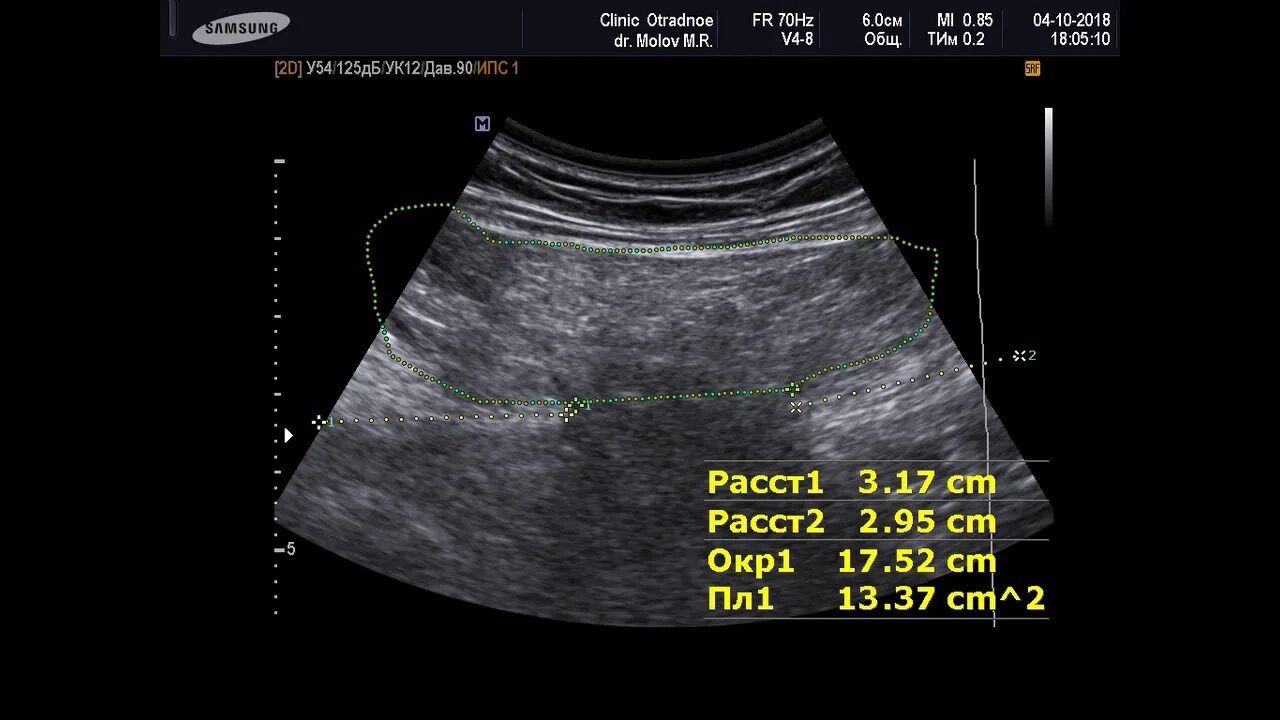

Грыжа спигелиевой линии